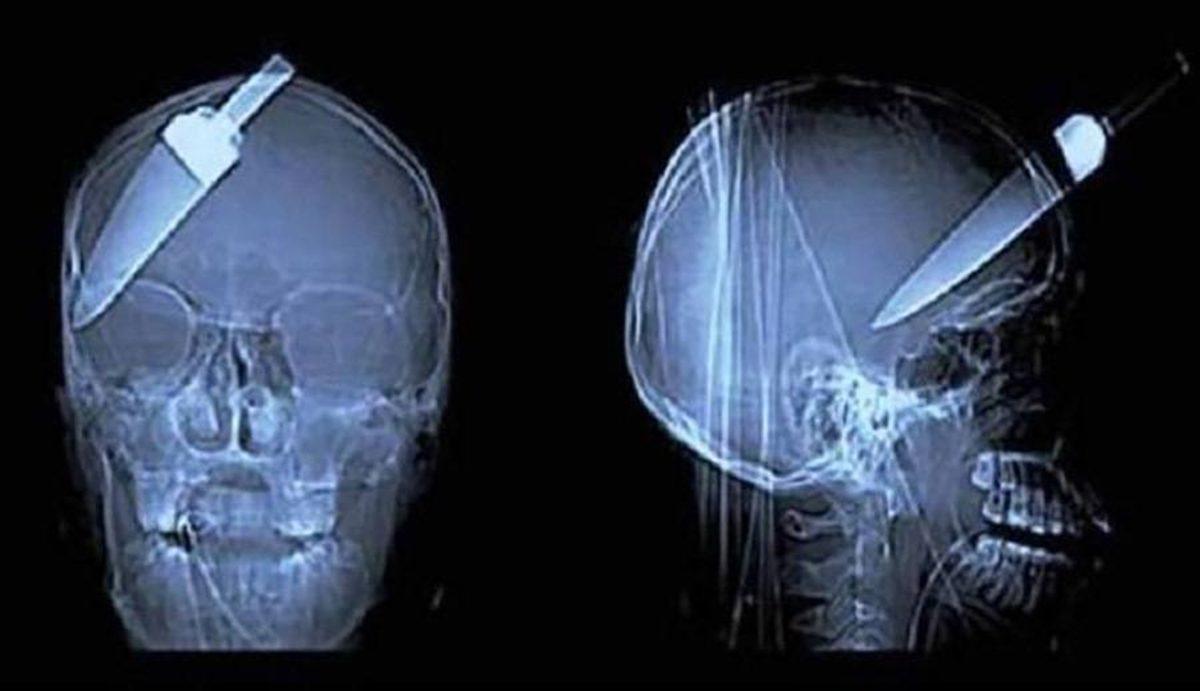

- Ters giden bir soygun sonucunda kafasına bıçak saplanan bir adam.

- Bir adamın arkasından atılan ateş maşası, arkadan girip önden çıkmış.